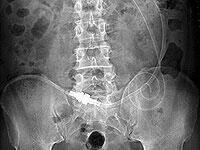

55 歳、男性、糖尿病の患者で1月 26 日に導入後の写真です。

2004 年5月9日、カテーテル先端は左腸骨

2004 年5月 25 日、カテーテル先端は臍部

2004 年6月 17 日、カテーテル先端は左腸骨

2004 年7月8日、カテーテル先端は右上腹部

2004 年8月3日、カテーテル先端は左腸骨

寝たきり患者では膀胱直腸窩より肝臓のある上腹部が低いため上腹部へ移動する場合があります。

写真7は 72 歳、女性、糖尿病で卵巣腫瘍切除術後、胆摘後。

下行結腸と壁側腹膜の間の溝にカテーテル先端が固定されています。

普段、横になっていることが多いとこの位置にカテーテル先端が移動しますが、左下側臥位でバッグ交換すると注排液の異常は生じません。